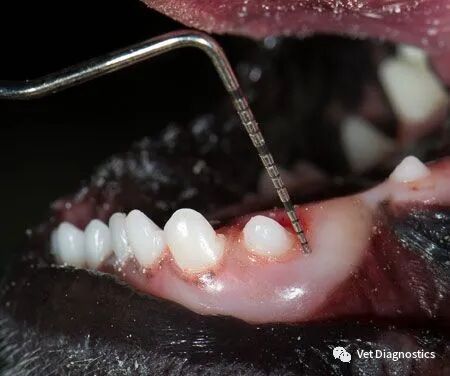

图1B.牙周探针插入狗的部分萌出的左下颌犬齿之前。

为什么牙医不用开口器兽医牙科基础知识:N代表NO_https://www.jmylbn.com_新闻资讯_第3张

图1C.10mm牙周袋;牙龈切除术、牙龈粘膜手术或拔牙指征。